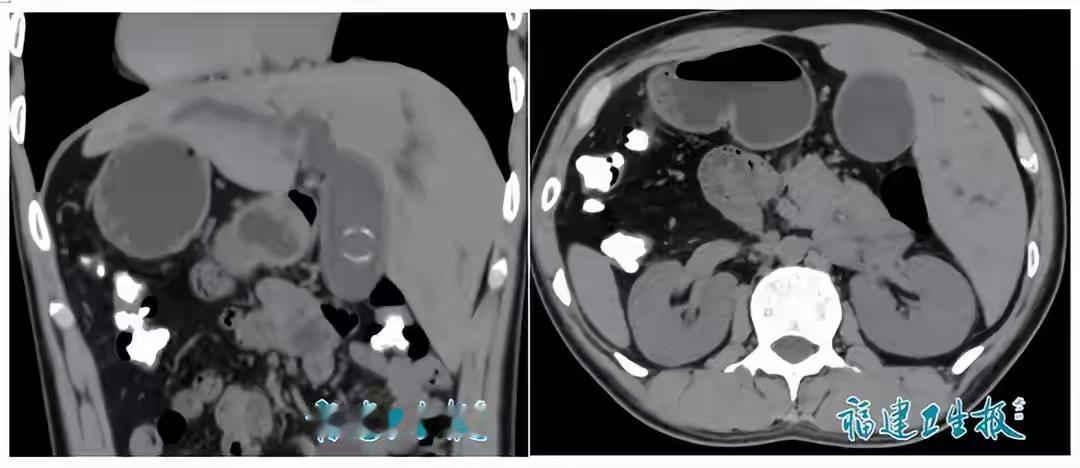

罕见!福建发现1例“镜面人”,医生:全球仅百万分之一 “医生,我的心脏好像跳得有点奇怪。”当23岁的小陈(化名)因腹痛就医时,医生看着影像报告,反复确认了三次——这不是医学错误,不是设备故障,而是一个活生生的“镜面人”,体内脏器位置与正常人完全相反,犹如在镜像世界中生活。 数据显示,这种全内脏反位发生概率仅为百万分之一。它不一定会带来健康问题,很多人甚至终生不知。小陈这次就医,才意外揭开了这个隐藏了23年的生命密码。 一、生命的“独家定制”:每个人都是奇迹 当我们为这百万分之一的概率惊叹时,其实每个人都携带着生命的“独家签名”。你的指纹、虹膜、DNA排列组合,都是宇宙中独一无二的存在。这种罕见的“镜面现象”,不过是生命多样性画卷中,一抹格外引人注目的色彩。 现代医学已经能够通过精细的影像技术,为这样的特殊结构制定个性化治疗方案。医生特别提醒,虽然“镜面人”可以健康生活,但就医时一定要主动告知医生自己的特殊情况,这是对自己生命的负责。 二、寻找内心的“镜面特质”:我们都与众不同 在这个追求“标准化”的时代,我们习惯隐藏自己的“不同”——也许是独特的思维方式,也许是格格不入的兴趣爱好,也许是内心深处那份不愿妥协的坚持。 小陈的身体是生理上的“镜面人”,而我们每个人,都可能拥有心理上的“镜面特质”:那些让你区别于他人的思维方式、情感反应、价值取向。社会这台大机器试图把我们打磨成标准零件,但正是那些“不标准”的部分,构成了真实的、有血有肉的“我”。 三、拥抱生命的“不对称美” 自然界的对称令人惊叹,但真正的美感常常存在于微妙的“不对称”中。生命的奇妙之处恰恰在于它的不可复制性和多样性。小陈的脏器位置虽然与常人相反,却依然和谐运作,维持着生命的平衡。 这像极了我们每个人的生活——也许你的人生轨迹不符合社会“标准路径”,你的选择让旁人看不懂,你的节奏与众不同。但正如“镜面人”的脏器功能完好无损,只要你找到内在的平衡点,这种“非常规”反而可能成为你独特的优势。 四、从“镜面人”到“镜像社会”:我们都需要一面镜子 “镜面人”现象最深刻的社会隐喻在于:我们都需要一面镜子,去看见那些“看不见的自己”。 在我们的社会角色和真实自我之间,常常存在着一种“镜像关系”。我们在职场中扮演着职业角色,在家庭中承担着亲属角色,但哪个才是最真实的你?当这些角色与内心渴望产生冲突时,你会如何选择? 小陈的案例像一面特殊的镜子,照见了医学的边界,也照见了我们对“正常”的狭隘定义。当一个社会能包容百万分之一的“镜面人”,它是否有足够胸怀容纳那些思想上、生活方式上“与众不同”的少数? 生命的常态本就是参差多态。我们赞颂罕见,却往往畏惧不同。 每一个“镜面人”的发现,都是在提醒我们:在追求共性的世界里,请为自己那份独特的“不对称”保留空间。因为正是这些微小差异,让人类整体如此强大而美丽。 你身边是否也有这样“与众不同”却活出精彩的人?你是否也曾隐藏自己的“镜面特质”以适应环境?在评论区,期待听到你独特的生命故事。